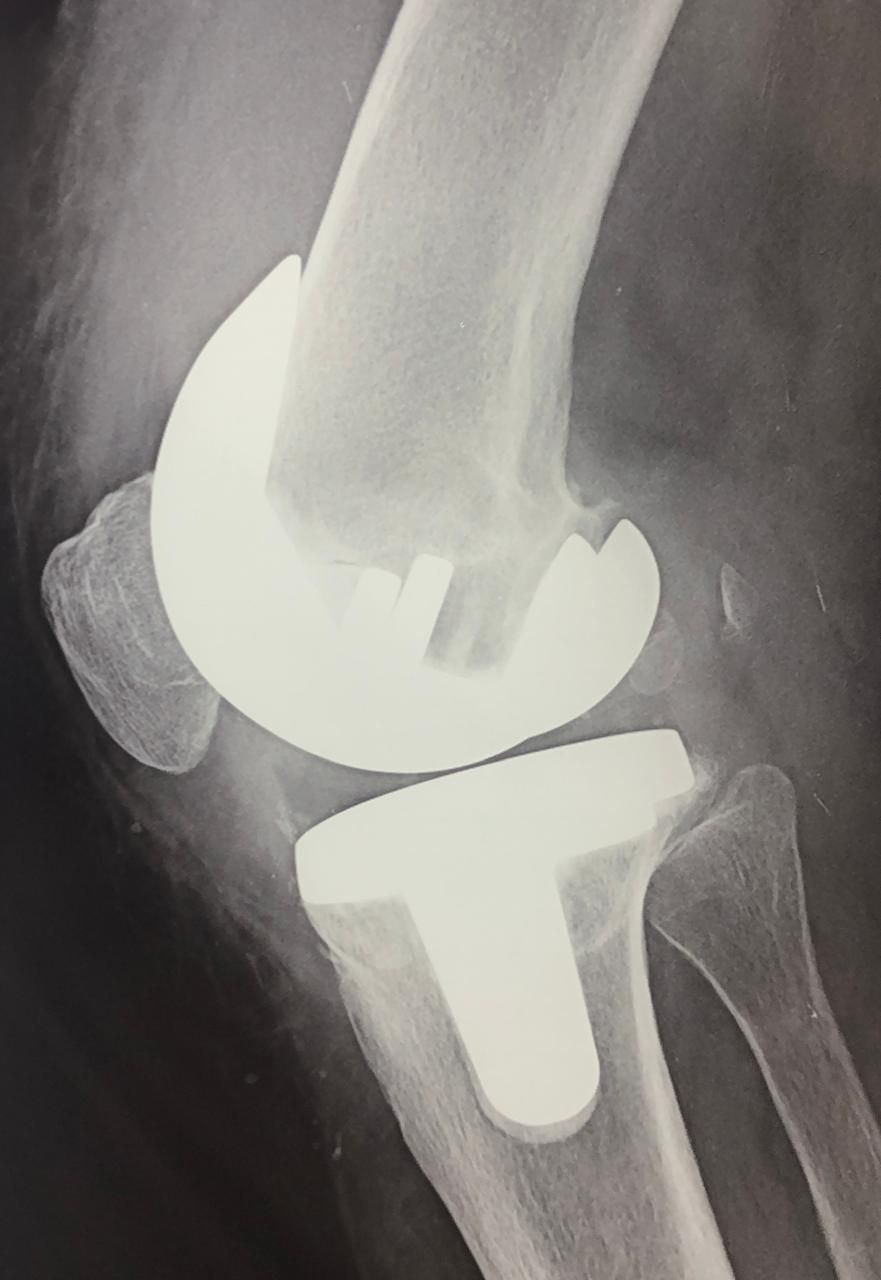

Cada caso es valorado a profundidad para proponer tratamientos conservadores (rehabilitación, ejercicios, ortesis) o procedimientos quirúrgicos cuando son necesarios, como artroplastías (colocación de prótesis articulares) o cirugías mínimamente invasivas como la artroscopía.